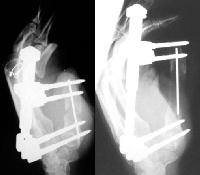

Initial and final result, with an intercalated bone graft.

Interim result. Flap debulking has since been performed.